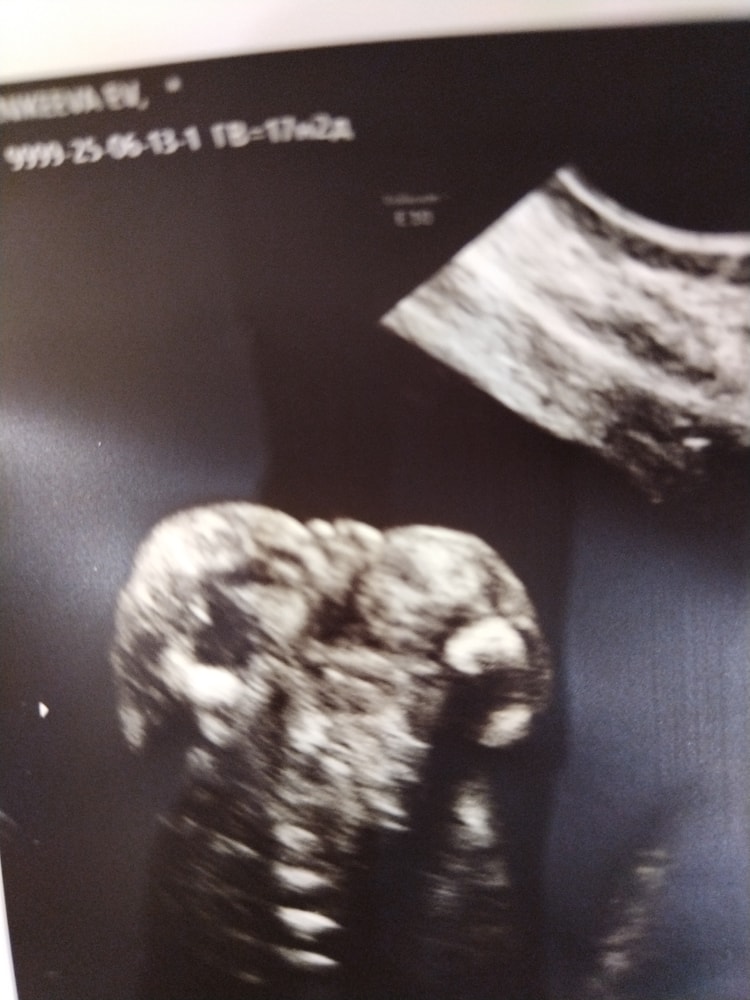

У меня

фото очень похоже на ваше, сегодня сказали девочка)

Вот это я понимаю ))) точность фото ))) пирожок так пирожок )